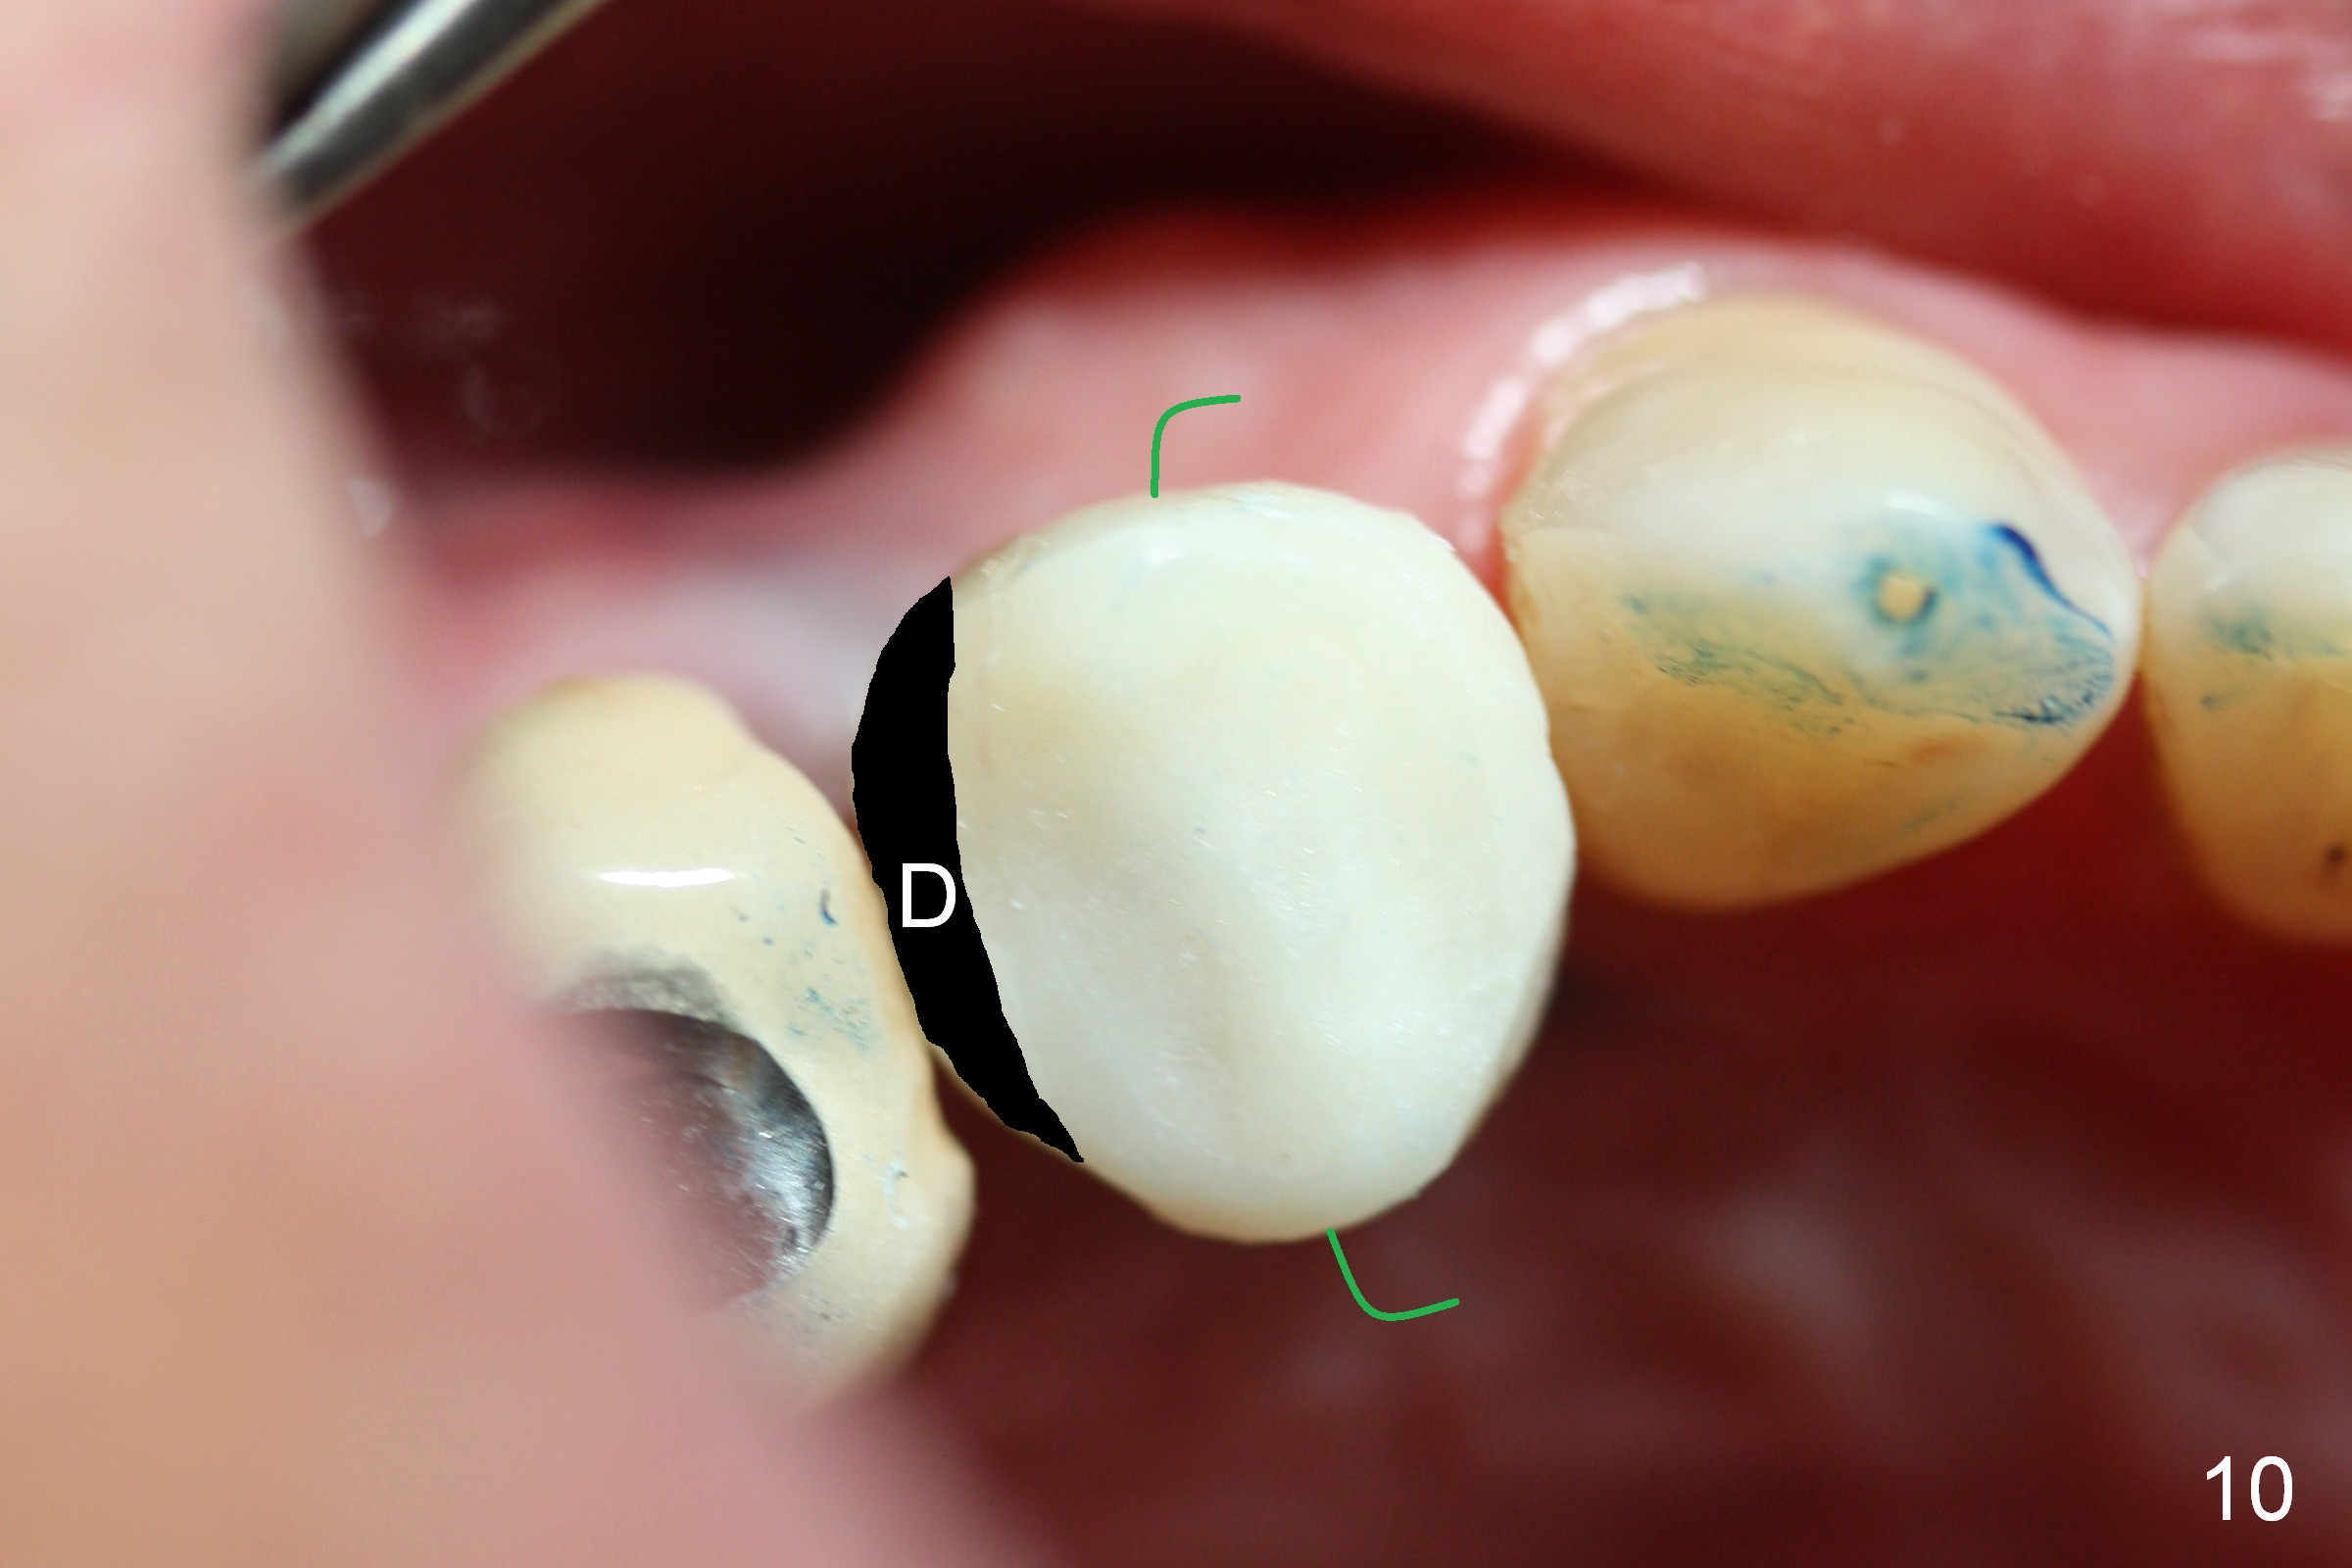

The distal surface of the provisional will be reduced (Fig.9,10 D), whereas the occlusal surface will be increased (Fig.9 O). If needed, the occlusal surface of the distalized tooth #4 will be reduced (Fig.9 red area) so that there is no interference for tooth to move. Hooks will be placed on the buccal and lingual surfaces of the provisional (Fig.10 green curved lines). Power chains will be placed on the hooks and wrapped around the tooth #4. In due time, the tooth will be mesialized (Fig.11 arrow). Implants at the sites of #2 and 3 will be placed in more appropriate positions.